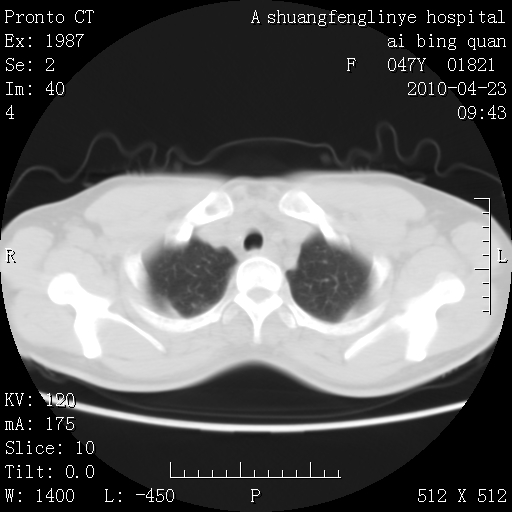

标题: CT25944:胸痛、气短、前几日高烧!肺Ca?请会诊! [打印本页]

标题: CT25944:胸痛、气短、前几日高烧!肺Ca?请会诊!

双肺多发结节,考虑转移瘤,肺癌肺转移不除外

双肺多发结节,部分密度较高,最大结节边缘光滑。临床有“胸痛、气短、前几日高烧”病史。首选考虑:右肺感染性病变!建议积极消炎后复查!